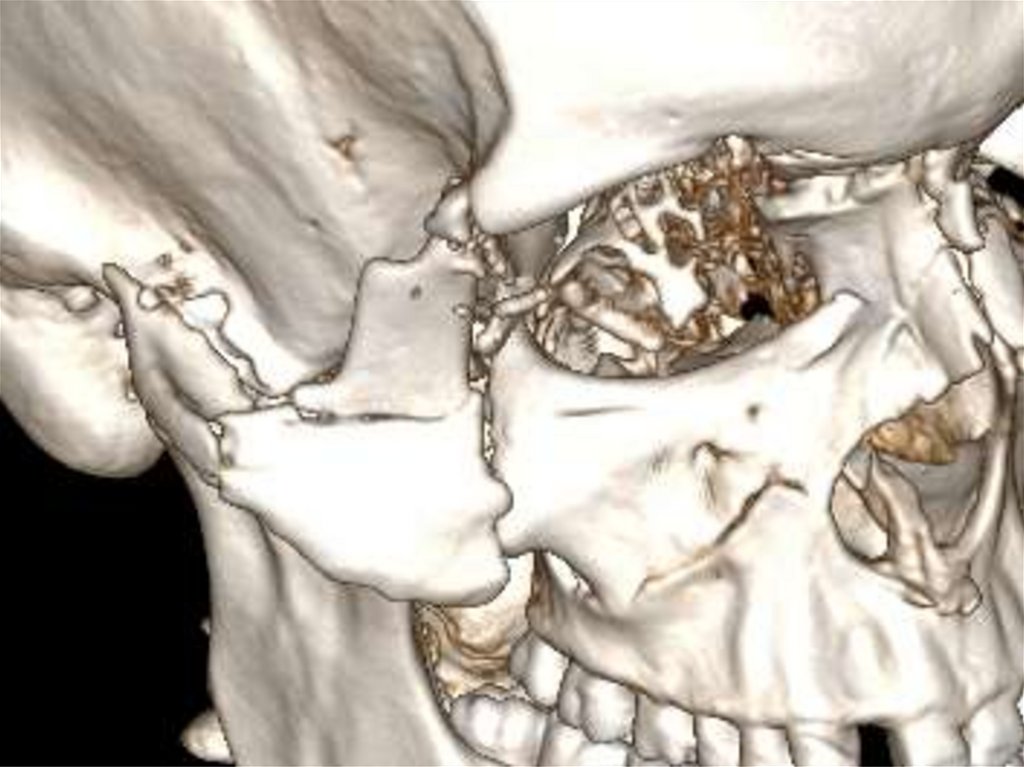

12. Клинический случай № 2! Поскользнулся, упал, потерял сознание, очнулся …

Пациент С. 40 лет.

Подглазничный,

(Субцилиарный)

доступ